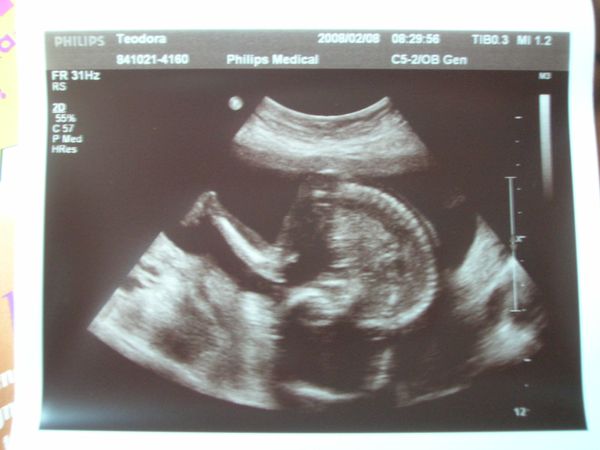

Én tegnap voltam 18 hetes genetikain ahol megerősítést kaptunk, hogy Dávidka Dávidka marad most már nincs mese

BPD:43mm THQ:39 mm ezeket mérték, az AFP értéke meg 1,21